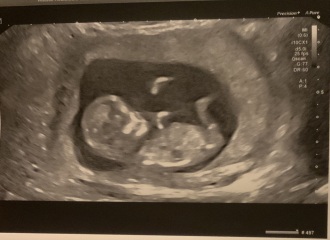

CluelessInLondon · 23/03/2024 16:55

12 week scan done for me - baby has grown ahead of schedule since my last scan and I've been dated at 13 weeks so technically now a September baby! We got to hear the heartbeat, which was amazing, and we could see it moving its mouth - I like to think it was saying hello to us. ☺️

@CluelessInLondon What a fabulous photo! We are now both due September babies! Though I'm a FTM so I expect an October baby anyway 😂

@CluelessInLondon so, so pleased for you! Such a lovely, clear scan as well.